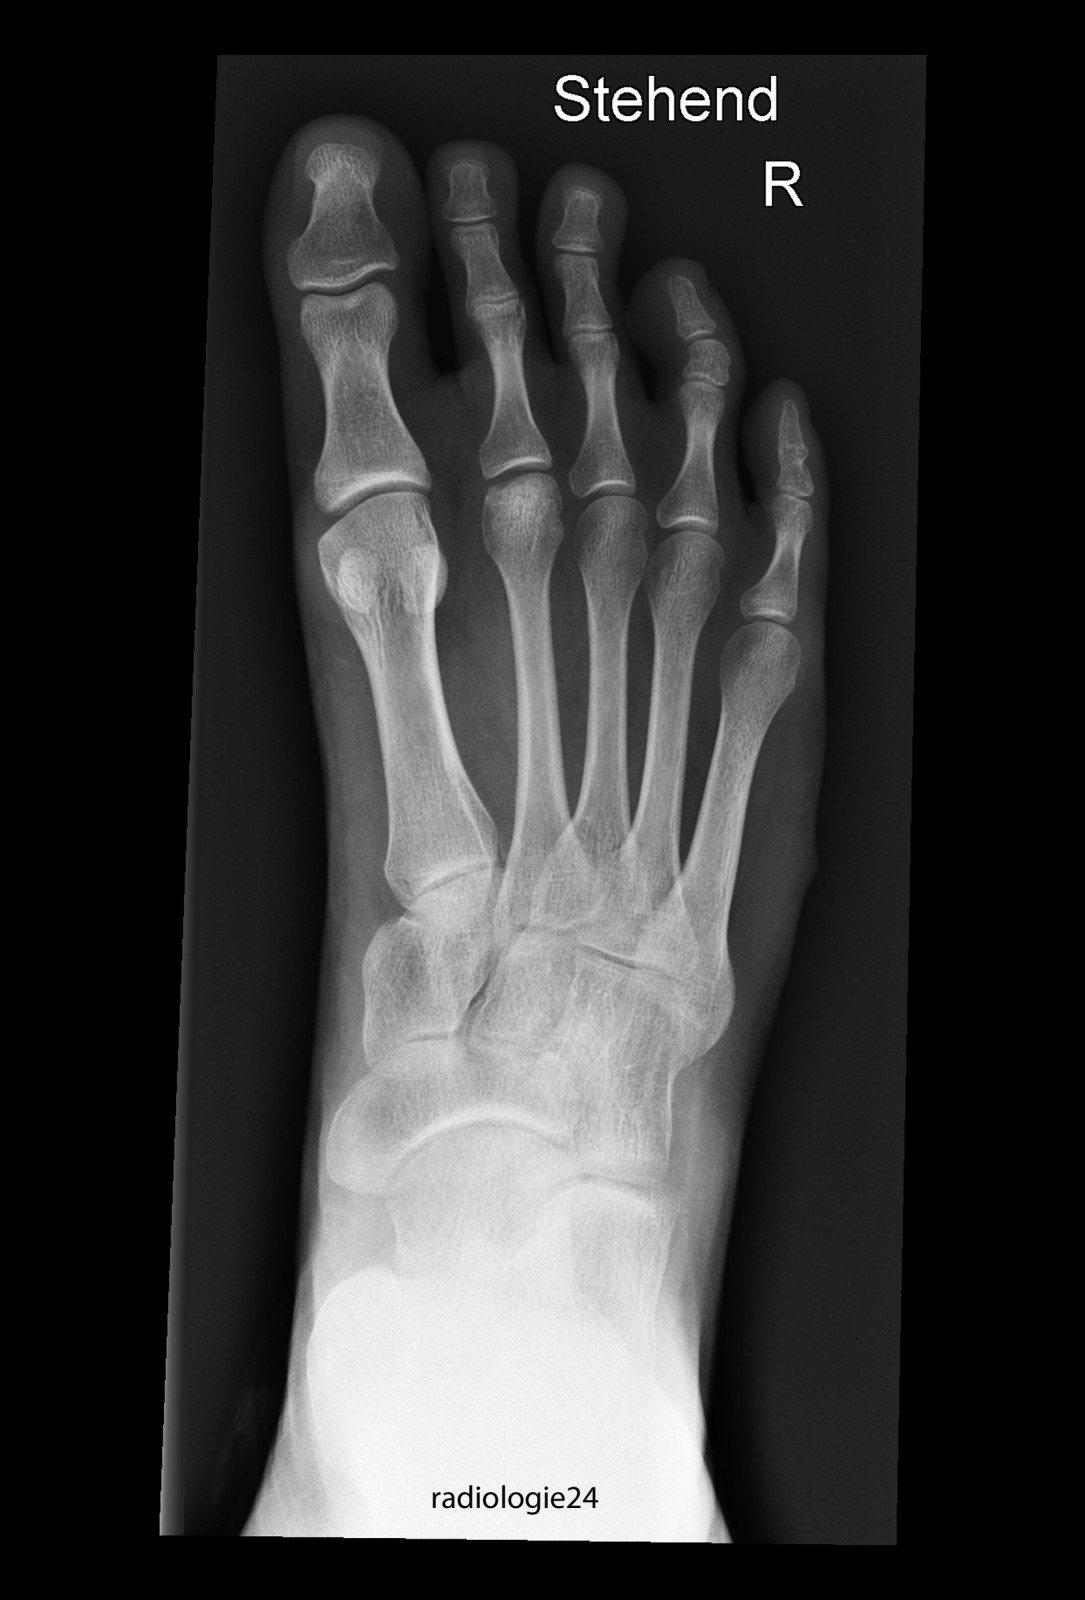

Röntgenfall des Monats November 2017 mit Auflösung

18 jährige Patientin Klinische Angaben: Schmerzen Vorfussbereich. Kein Trauma erinnerlich.

Bild vergrössern

Link zur Auflösung mit ausführlichem Befund

https://www.radiologie24.ch/radiologie-mediathek/roentgenfall_des_monats